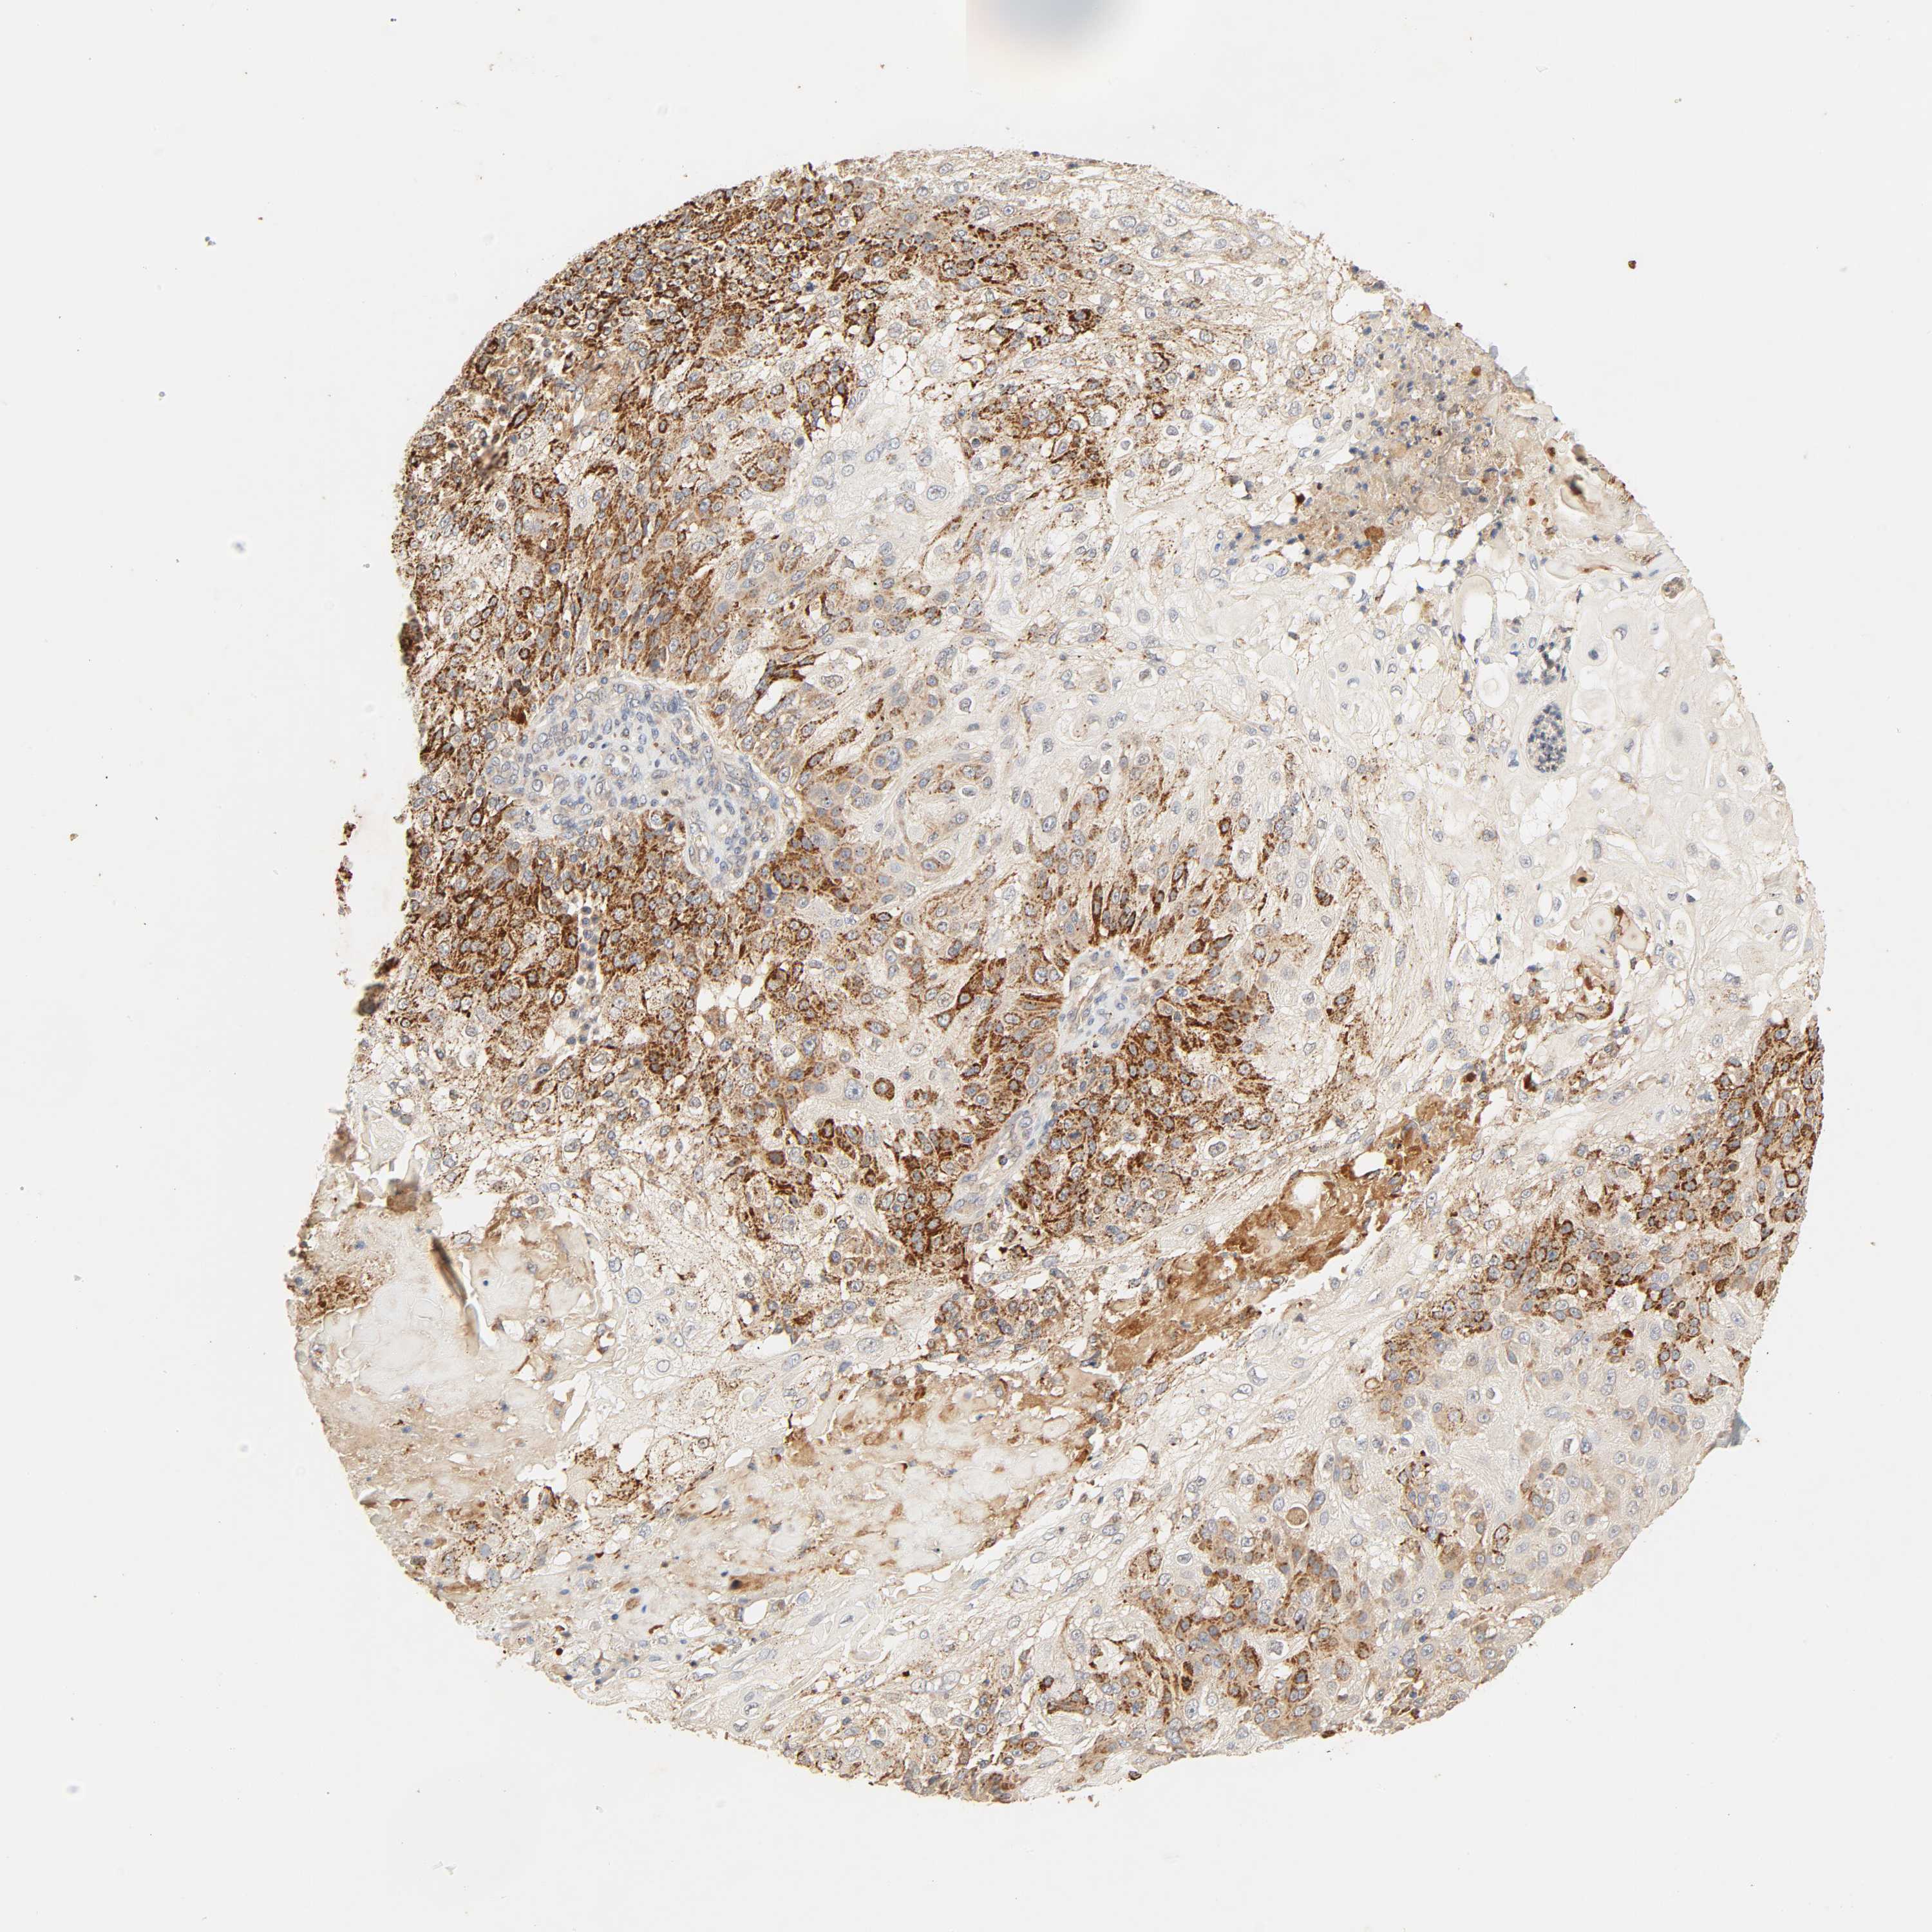

SKIN CANCER - Protein expressioni

A mouse-over function shows sample information and annotation data. Click on an image to view it in a full screen mode. Samples can be filtered based on level of antibody staining by selecting one or several of the following categories: high, medium, low and not detected. The assay and annotation is described here.

Antibody stainingi

Antibody staining in the annotated cell types in the current human tissue is reported as not detected, low, medium, or high, based on conventional immunohistochemistry profiling in selected tissues. This score is based on the combination of the staining intensity and fraction of stained cells.

Each image is clickable and will lead to virtual microscopy that enables deeper exploration of all samples and also displays staining intensity scores, fraction scores and subcellular localization as well as patient and tissue information for each sample.

Antibody HPA047825

Squamous cell carcinoma, NOS